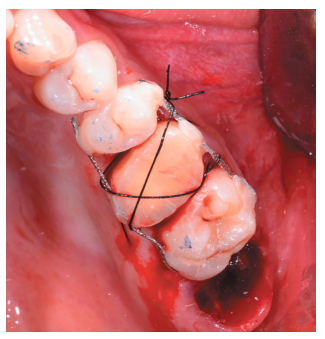

Caso clínico: se presenta el caso de un varón de 28 años, que acudió a consulta por la presencia de unos restos radiculares en localización de primer molar superior izquierdo. Se realizó un autotrasplante dental, siendo el diente donante el tercer molar superior izquierdo, que se trasplantó al alveolo del primer molar, mostrando buena evolución clínica y radiográfi ca.

Clinical case: a clinical case of a 28-yearold man is presented, who went to dental clinic for removal of left fi rst molar roots. An autotransplant was performed using left third molar as donor tooth, which was transplanted into fi rst molar alveolus, showing promising clinical and radiographic evolution.